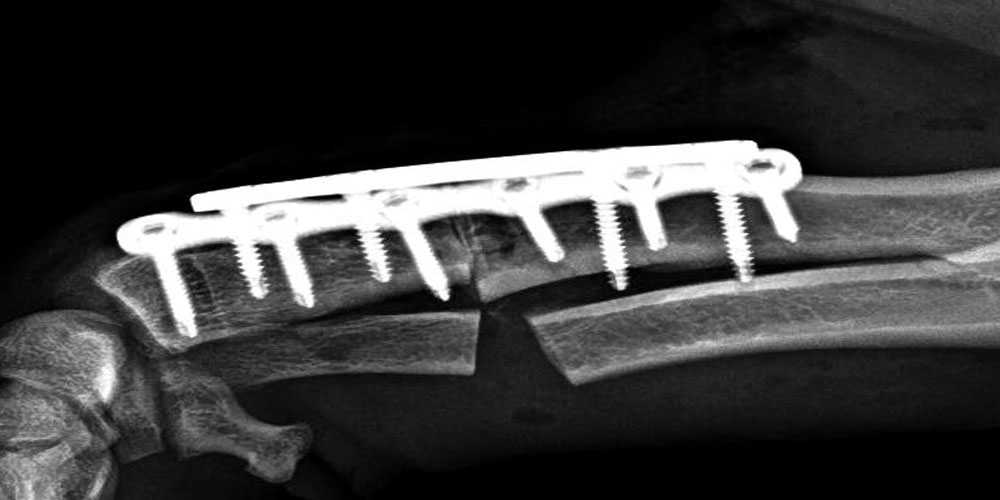

Gelenk- und Knochen

Die häufigste Lahmheitsursache der Hintergliedmaße beim ausgewachsenen Hund und auch älteren Katzen ist ein Riss des vorderen Kreuzbandes, oft begleitet von einer Verletzung des inneren Meniskus. Kreuzbandrisse führen zu Instabilität, Meniskusfolgeschäden, Gelenksentzündung und Arthrosebildung im Kniegelenk. Bei einem Kreuzbandriss des Hundes liegt meist eine chronisch-degenerative Erkrankung zugrunde, weniger das scheinbar akute Trauma. Abhängig von Größe, Gewicht und Alter Ihres Tieres, sowie dem Verletzungs- und Arthrosegrad des Kniegelenkes empfehlen und führen wir die Meniskusdiagnostik und die für Ihr Tier angebrachteste Kreuzband-Operation durch. Die mit von uns weiterentwickelte, moderne TTA Rapid Methode zur Kreuzbandbehandlung mit dem Titan Implantat der Firma R.Leibinger medical bietet eine sehr frühe Wiederbelastung der operierten Gliedmaße und schnellere Genesung Ihres Hundes und Ihrer Katze.